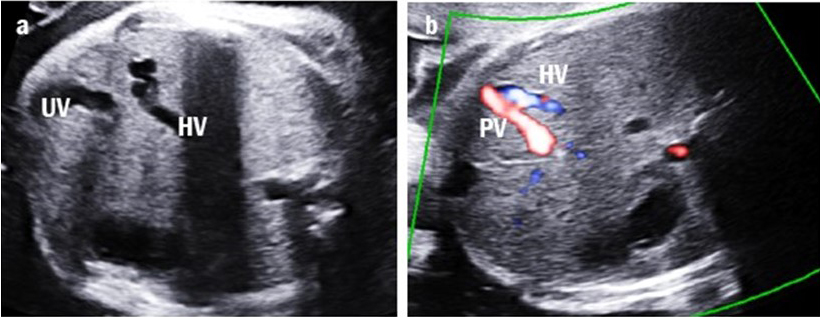

Four cases were classified as type IIIa UPSVS. They showed an abnormal connection between the PV and hepatic vein, which was observed as a tortuous and engorged vessel in the fetal liver (Fig. 4). However, the umbilical-portal-DV complex remained intact. Among these cases, three (75%) had birth weights below the 10th percentile and all had transient mild hyperammonemia. More importantly, none of them required shunt ligation surgery or liver transplantation.

Fig. 4.

Fig. 4.Intrahepatic portal-systemic shunt in case 11. (a) The tortuous and engorged hepatic vein (HV) is shown. (b) The intrahepatic portal vein (PV) is connected to the HV.